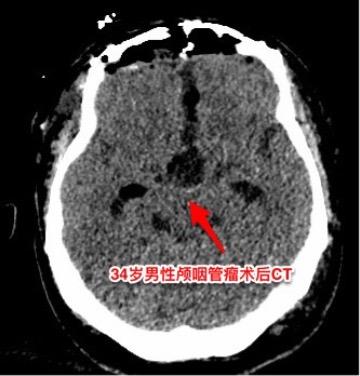

乳头型和造釉型颅咽管瘤的混合型存在吗?34岁男性,广东省惠州市人。一年前因视力下降发现颅咽管瘤,在广东省某医院行开颅手术切除一部分肿瘤。肿瘤复发了来三博脑科医院找我治疗。 第一次手术后病理报告考虑是乳头型颅咽管瘤和造釉型颅咽管瘤的混合型(太罕见了)。手术中还留置了一个动脉瘤夹子、一个Ommaya囊。 昨日作了开颅手术,术中看见肿瘤血供十分丰富,和第三脑室壁及大脑后动脉粘连。手术经历9.5个小时,肿瘤得到完全切除。术后病人的精神状态及四肢活动均很好。希望以后肿瘤不复发。等待病理